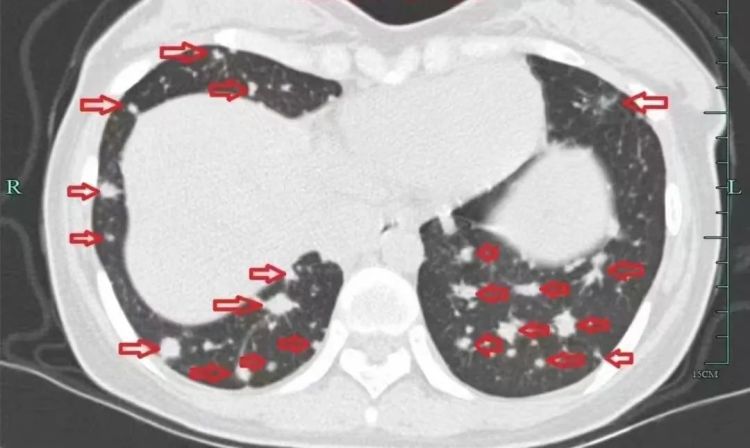

治疗前

入院后,小谢完善了抽血化验及肺部CT、肝脏磁共振等检查,但结果却极其凶险,肺部转移灶如“满天星”,肝脏肿块压迫胆管导致胆红素水平飙升,整个人都“黄”得一塌糊涂。

几个月后,她的病情逐渐好转,肺部的“满天星”也消失了!小谢满心感激:“是丁主任救了我的命,让我重获新生!”